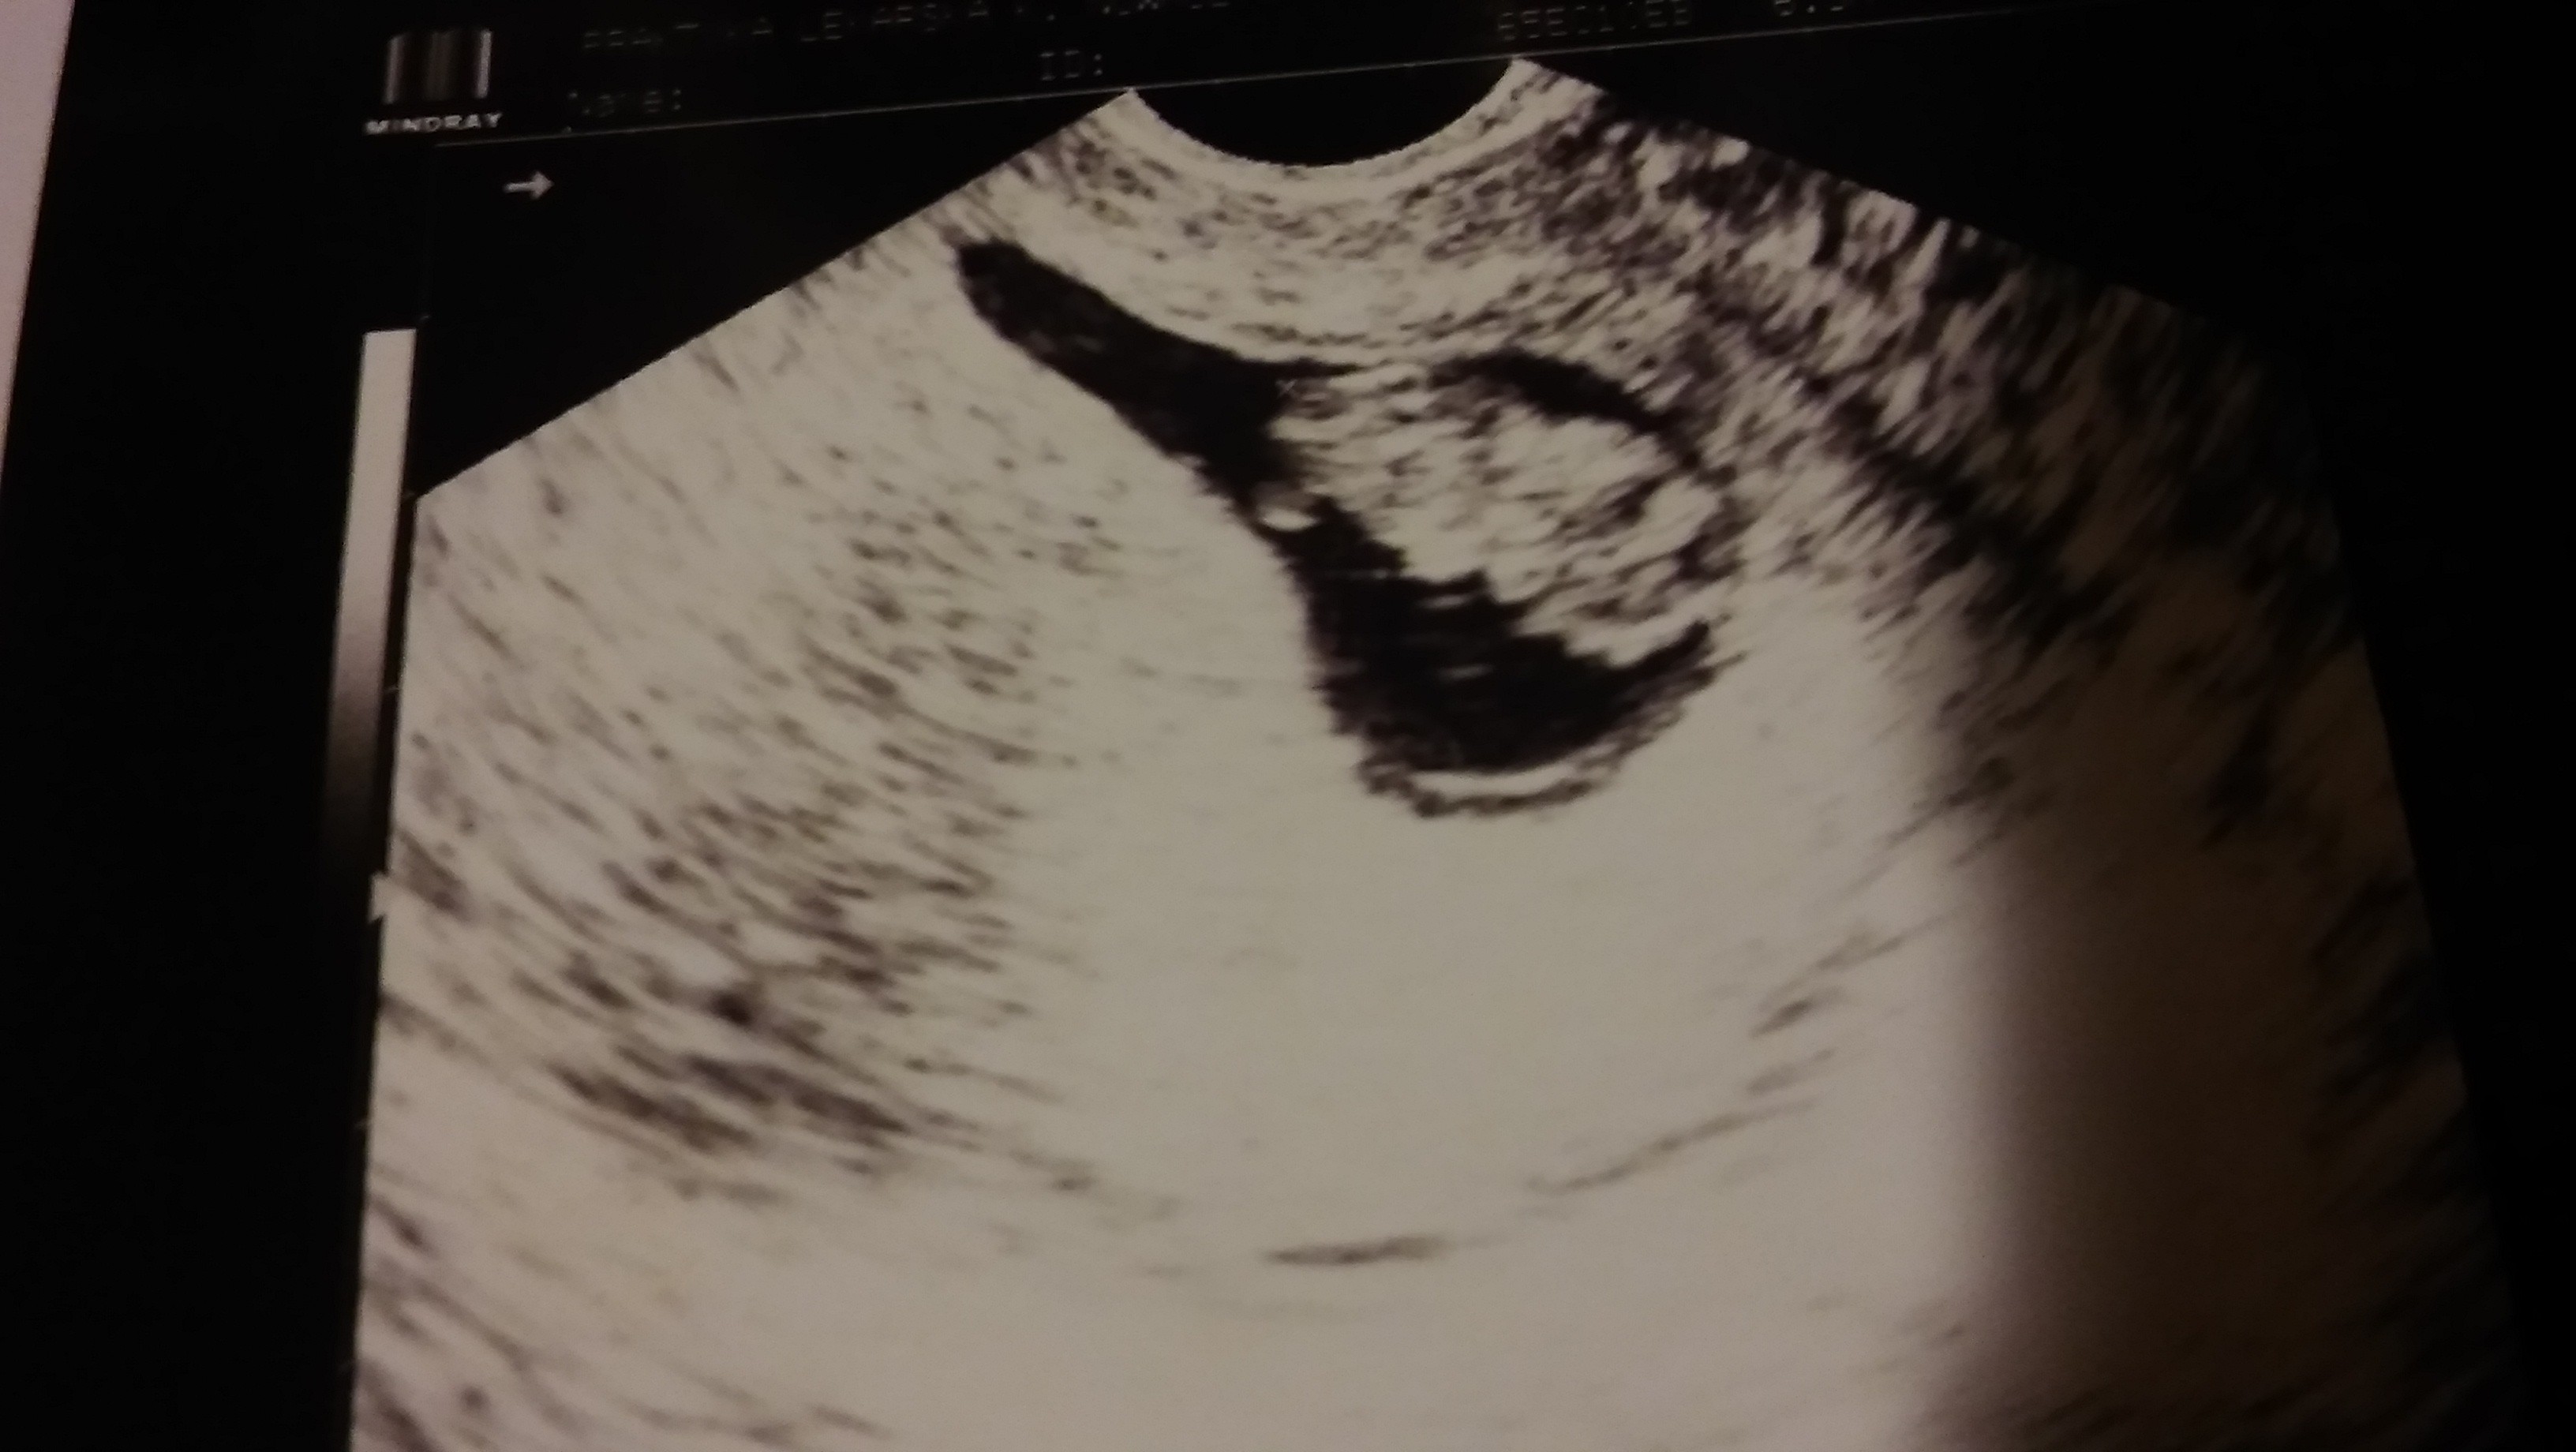

Twój mąż już widział maluszka?

Mój mąż widział dzidziusia 2 razy i bardzo się z tego cieszył chociaż często jest powściągliwy w okazywaniu uczuć